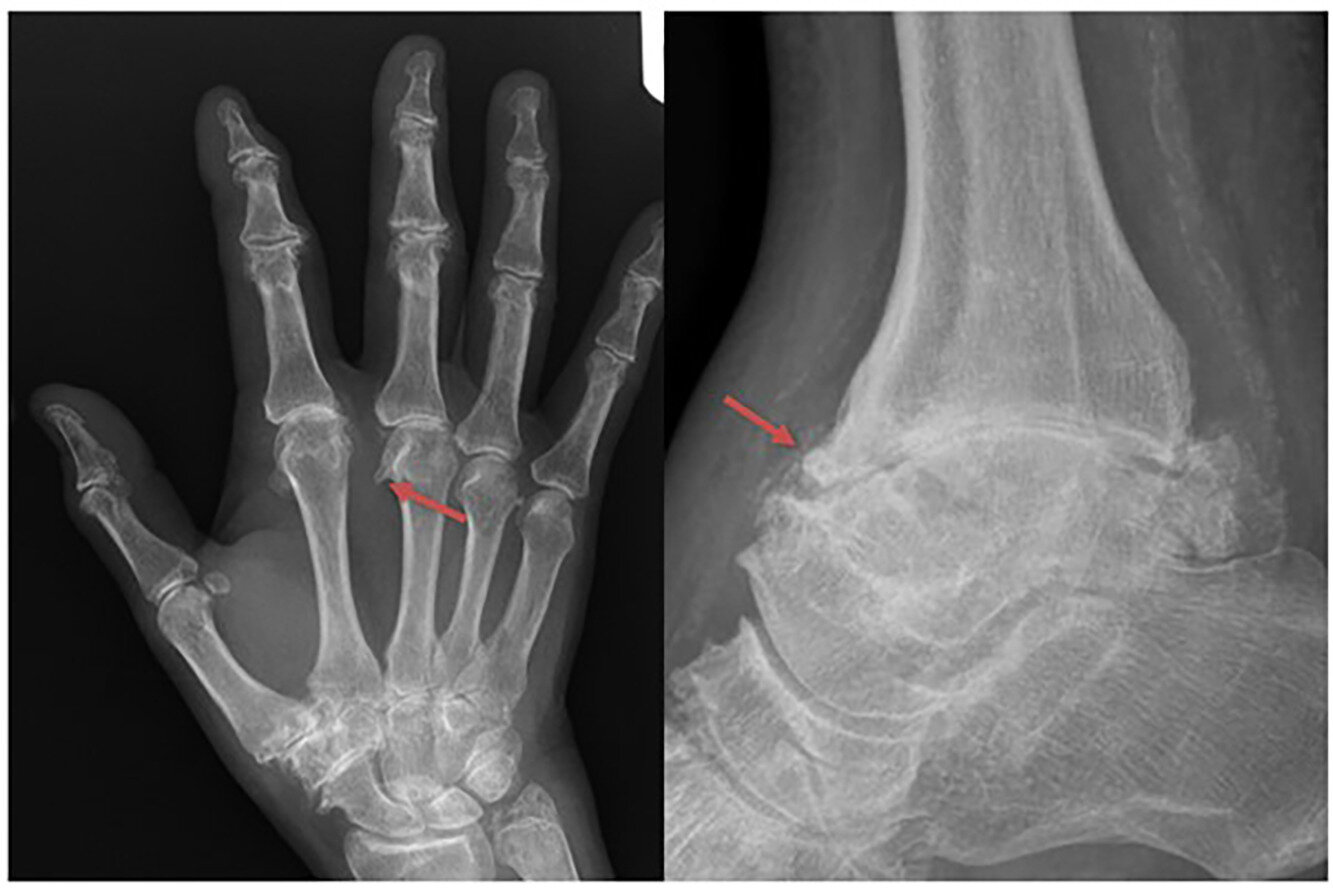

In the joints, excess iron appears to set off a cascade of damage that leads to stiffness, pain, and early-onset degeneration—especially in the hands, wrists, and ankles. Yet, until now, the exact relationship between iron overload, hepcidin deficiency (a hormone that controls iron balance), and joint destruction has remained murky.

Clinicians often struggle to distinguish HA from osteoarthritis or calcium pyrophosphate deposition disease (CPPD) because the symptoms and X-ray findings overlap. Without specific criteria, research into the mechanisms, prevalence, and treatment of HA was stunted.

The result of this effort is a points-based classification system that blends scientific rigor with practical usability. Designed for people with joint pain who also have C282Y homozygous mutations and evidence of iron overload, the model uses eight key variables. These variables capture both clinical symptoms and imaging findings, particularly focusing on the metacarpophalangeal (MCP), distal interphalangeal (DIP), and ankle joints—areas often affected in HA.